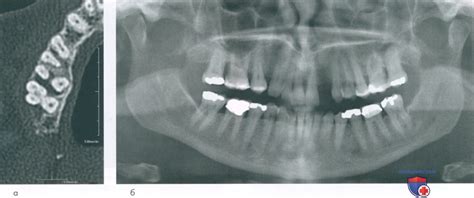

Рентгенологическая оценка поражений пародонта в...